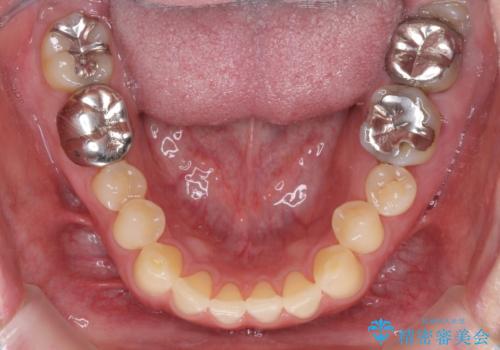

受け口を治す ワイヤー装置での矯正治療

歯並びや口元の印象、奥歯の咬み合わせから、非抜歯にて矯正治療を行うこととしました。

インプラント埋入による仮歯の装着や、前歯の反対咬合の改善は比較的スムーズに達成されましたが、舌突出癖などの影響による、歯列全体のスペースを閉じることが難航し、期間がかかってしまいました。